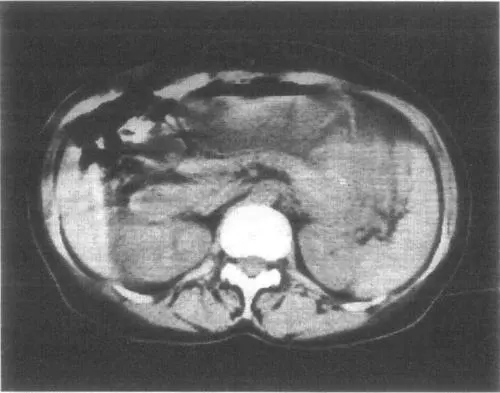

1.3.CT掃描顯示 腫瘤位于后縱隔,多靠近椎旁,腫瘤邊界清楚。呈圓形、卵圓形,良性或惡性腫瘤部分病例可以有分葉。多發(fā)性神經(jīng)纖維瘤病,CT掃描的檢出率往往比普通X線胸片高。

1.4.磁共振成像(MRI) 增強(qiáng)的T1和T2的影像可顯示:神經(jīng)纖維瘤有一高密度特征性外周區(qū)和中等密度的中央?yún)^(qū),而神經(jīng)鞘瘤為不均質(zhì)的高密度區(qū)。CT或MRI可以確定,腫瘤侵入脊椎管的情況,后者還可以用來確定累及范圍。然而目前通常使用增強(qiáng)的脊髓X線檢查來了解腫瘤入侵的情況。如為一側(cè)胸內(nèi)巨大神經(jīng)源性腫瘤,X線片、CT片均可顯示巨大腫瘤占滿整個(gè)胸腔,縱隔向健側(cè)移位,氣管移位,受壓或變窄,患側(cè)肺受壓,常見患側(cè)胸內(nèi)積液。